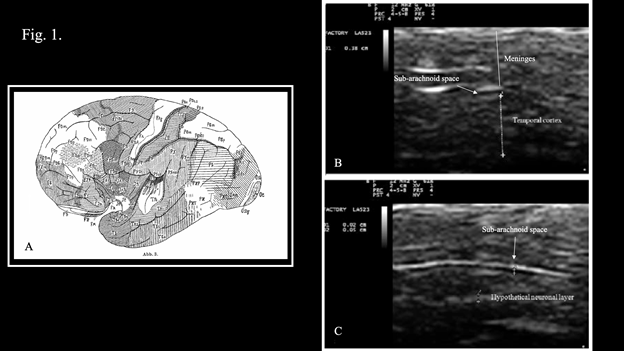

Step 2 of the procedure consists of diagnostic ultrasonography that has the role of refining the diagnostic hypotheses put forward by clinical examination as described in detail in Klinghardt and Ruggiero.10 In case of Neuro-COVID-19, transcranial ultrasonography of the temporal lobe of the brain has the primary role of early identification of the neuropathological findings of COVID-19 that are constituted by edema, meningeal congestion, hemorrhages, infarcts, and hematomas.2 The methodology for transcranial ultrasonography described in Ruggiero et al.,14 and in Bradstreet et al.,16 is particularly suited for this scope as it allows detailed visualization of brain structures as demonstrated in Figures 1 and 2. Figure 1 shows ultrasound visualization of normal meninges and temporal cortex. The meninges show the appearance of a structured array of layers with alternating hyper- and hypoechoic lines. The sub-arachnoid space shows the appearance of a horizontal “track”. An anechoic linear space (black in the figure) is paralleled by two hyper-echoic (white) stripes (Figure 1C). The inner anechogenicity of this structure is due the presence of a minute film of liquor that appears black in ultrasonography and shows a thickness of 0.2 mm. The sub-arachnoid space is situated parallel to the temporal squama, and signals the border between the meninges and the cortex. Thickness of the sub-arachnoid space in its entirety was around 0.6 mm (not shown). The thickness of the temporal cortex was calculated by the program of the Esaote machine in 3.8 mm (Figure 1B). Such a thickness was indirect confirmation of the anatomical position of the probe in correspondence of the areas of the temporal cortex that are designated TG and TE (see Figure 1, panel A for anatomical reference). These are the areas involved in the control of the movements of the eyes and in maintaining balance while standing (area TE), as well as in the control of social behavior, mood and decision making (area TG). It is worth noticing that these areas of the temporal lobe are among those that show alterations in Neuro-COVID-19.17 The high degree of spatial resolution enabled visualization of sub-millimetric structures (Figure 2A), that correspond to the neuronal layers of the cortex as represented in Figure 2B.18,19 The hyperechoic structures correspond to irregular cytological architecture that is characteristic of those layers where there is high density of neurons whose soma have irregular shape. The echogenic profile depicted in Fig. 2 A, is superimposable to that obtained by Nissl histologic staining, a classical method to visualize the soma of brain neurons. It is worth noticing that most of the studies on neuroimaging in COVID-19 were performed using computed tomography (CT) or magnetic resonance imaging (MRI),20 two techniques that are expensive, time-consuming, have to be performed in hospitals or specialized structures, involve the use of electromagnetic radiations (ionizing radiations in the case of CT), and cannot be performed in the comfort of the patient's home using portable, low-cost machines. Therefore, given the amount of information obtainable with transcranial ultrasonography, and considering the obvious advantages of this technique, it is proposed to incorporate transcranial ultrasonography in the study of Neuro-COVID-19 either as an independent exam or integrated in the procedure described in Klinghardt and Ruggiero.10

Figure 1 Transcranial ultrasonography of the temporal lobe of the brain

A. Cytoarchitectonic map from Constantin von Economo's original work. Constantin von Economo. Der Zellaufbau der Grosshirnrinde und die progressive Cerebration. Ergebnisse der Physiologie. 29, 1, 83-128. 1929. doi:10.1007/BF01942021, Public Domain, https://commons.wikimedia.org/w/index.php?curid=3640121.

B. Ultrasonographic appearance of the meninges, the sub-arachnoid space and the temporal cortex. Thickness of the cortex of the temporal lobe is consistent with that of the TE and TG areas.

C. Focalization on the sub-arachnoid space. An hyperechoic layer, hypothetically corresponding to a cortical neuronal layer of 0.5 mm is evidenced in the depth of the temporal lobe.